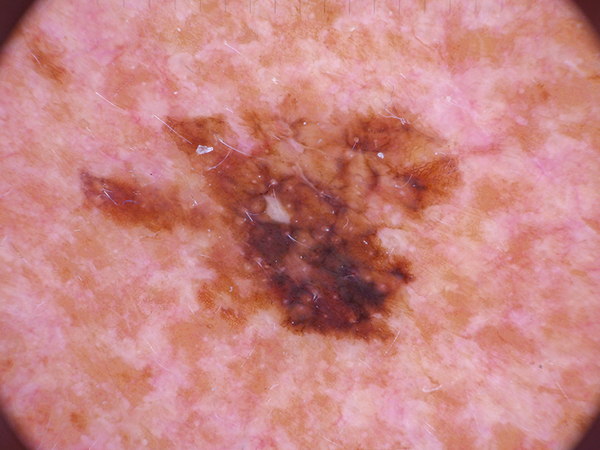

Testing Model: Skin Cancer

Classifies skin cancers (Always consult a medical professional)

Trained on: 10,015 images

Try a sample image (drag it into the box):

Actinic keratoses

Basal cell carcinoma

Benign keratosis-like lesions

Dermatofibroma

Melanoma

Melanocytic nevi

Vascular lesions